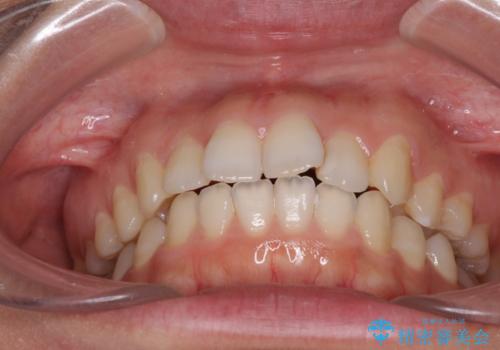

- 前歯のデコボコを気にして来院された患者様です。

目立たないことを最優先にしたいとのことで、デコボコは軽度であったことから、インビザラインにて矯正治療を行うこととしました。

骨格的に下顎骨が左にずれており、上下の正中一致は困難ではありましたが、IPR(歯と歯の間を削る)や後方への移動など組み合わせて、できる限り改善しました。

インビザラインはマウスピースを外している時間が長いと、長期間使用しても前歯のデコボコはあまり改善されません。こちらの患者様は治療期間が長くなり、装着時間が短くなってしまったことで、気になる部分の改善により長期間を要するようになってしまいました。